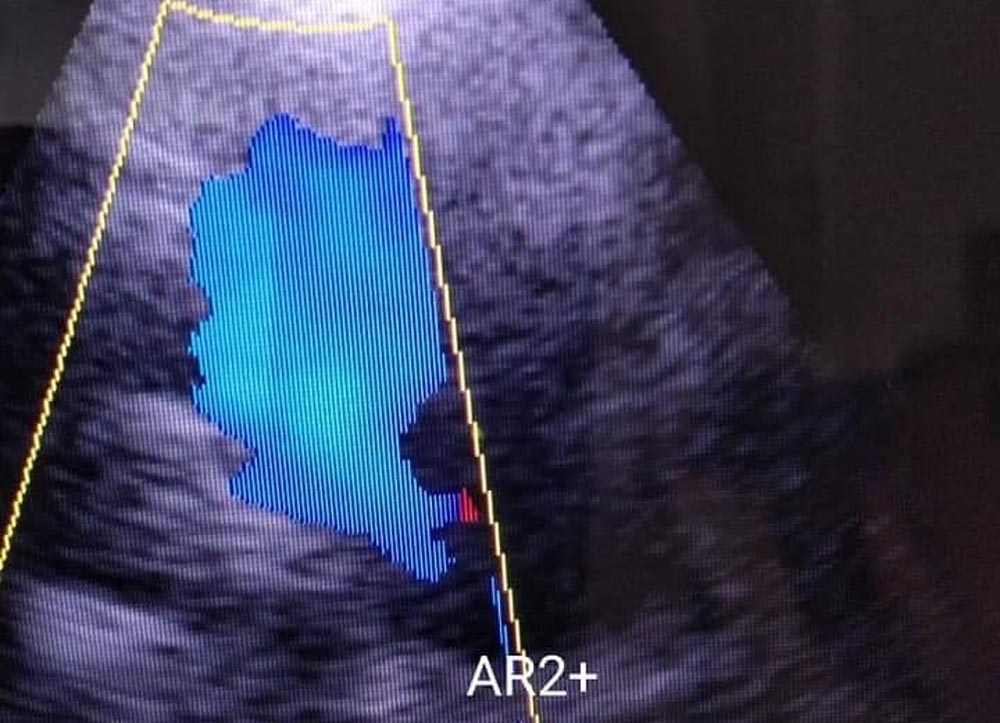

Клиничката презентација е во зависност од степенот на регургитација од асимптоматска до болки зад градна коска, срцебиење, малаксаност, висок систолен, а низок дијастолен притисок, постоење на дијастолен шум на ниво на точката на Боткин-Ерб, Corigan-знак со јаки пулсации на југуларните вени на вратот, Quinke знак со притискање на врв на ноктите и промена на блефило со црвенило. Ехокардиографски постои зголемување на дијаметар на v.contracta над 3 мм, турбулентност на проток на ниво на аорта на collor doppler, ширина на џет во LVOT над 25 %,итн.